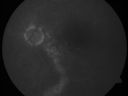

Chronic Central Serous Retinopathy - Gutter in Both Eyes - Treated with PDT - Visudyne814 views69-year-old man with blurred vision in the right eye for about three weeks. He had a similar episode about twenty years ago which lasted about six weeks. He is not taking any steroids. He takes Lupron injections for his prostate cancer every three months.

VISUAL ACUITY: Vision OD is 20/80

FU: Treated with PDT after 6 months of observation with success. Treatment was done to area between nerve and fovea at 1/2 fluence.